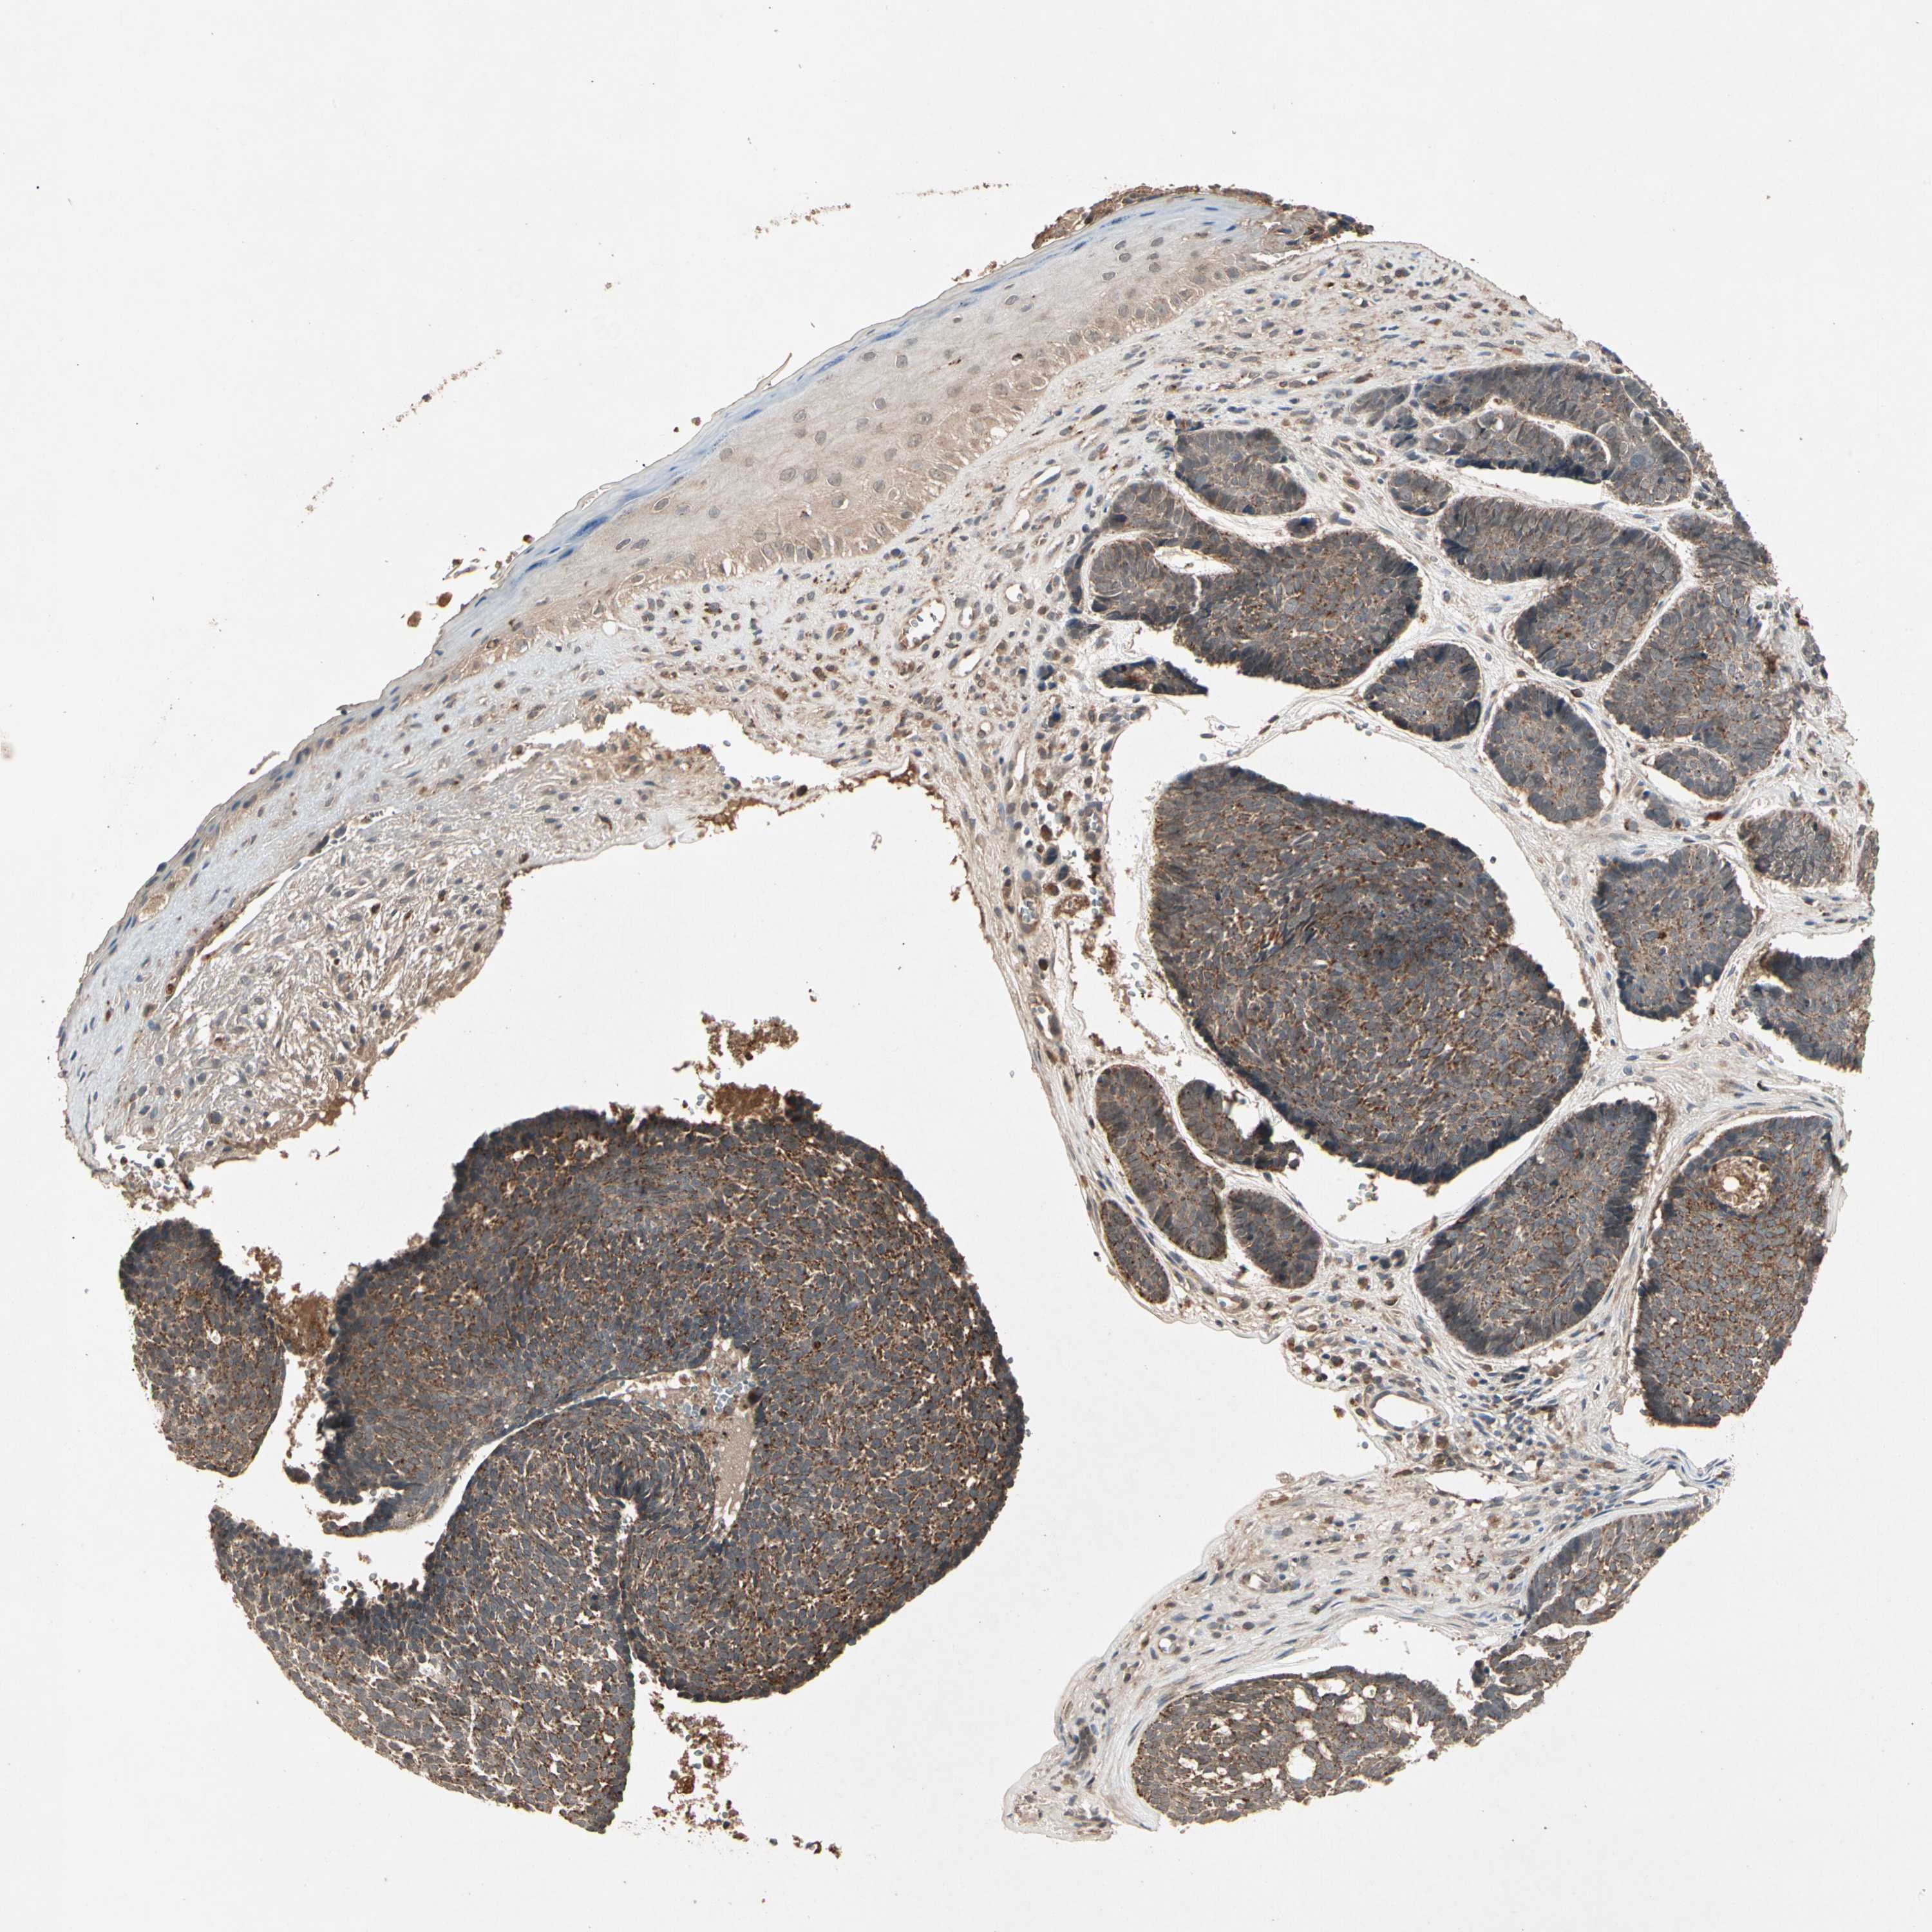

CANCER SKIN CANCER Show tissue menu

Basal cell and squamous cell cancer

SKIN CANCER - Protein expressioni

A mouse-over function shows sample information and annotation data. Click on an image to view it in a full screen mode. Samples can be filtered based on level of antibody staining by selecting one or several of the following categories: high, medium, low and not detected. The assay and annotation is described here.

Each image is clickable and will lead to virtual microscopy that enables deeper exploration of all samples and also displays staining intensity scores, fraction scores and subcellular localization as well as patient and tissue information for each sample.

Antibody HPA001393

Antibody CAB007766

Squamous cell carcinoma, NOS

Basal cell carcinoma

Squamous cell carcinoma, metastatic, NOS